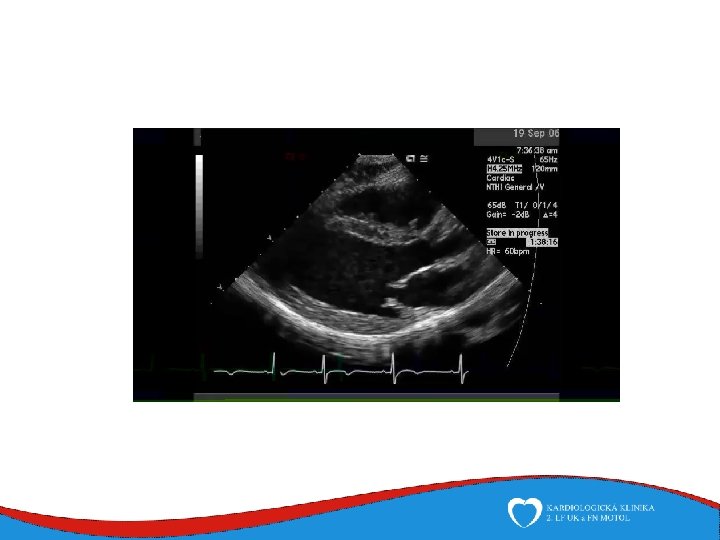

Echocardiography • • • Mainstay of valve disease diagnosis and follow-up Allows real-time measurement of chamber and wall diameters, ejection fraction assessment and functional valve evaluation Easily avaiable and repeated Essential in acute valve disease diagnosis No radiation harm Trans-esophageal echocardiography avaiable for patients with poor transthoracic sonographic window